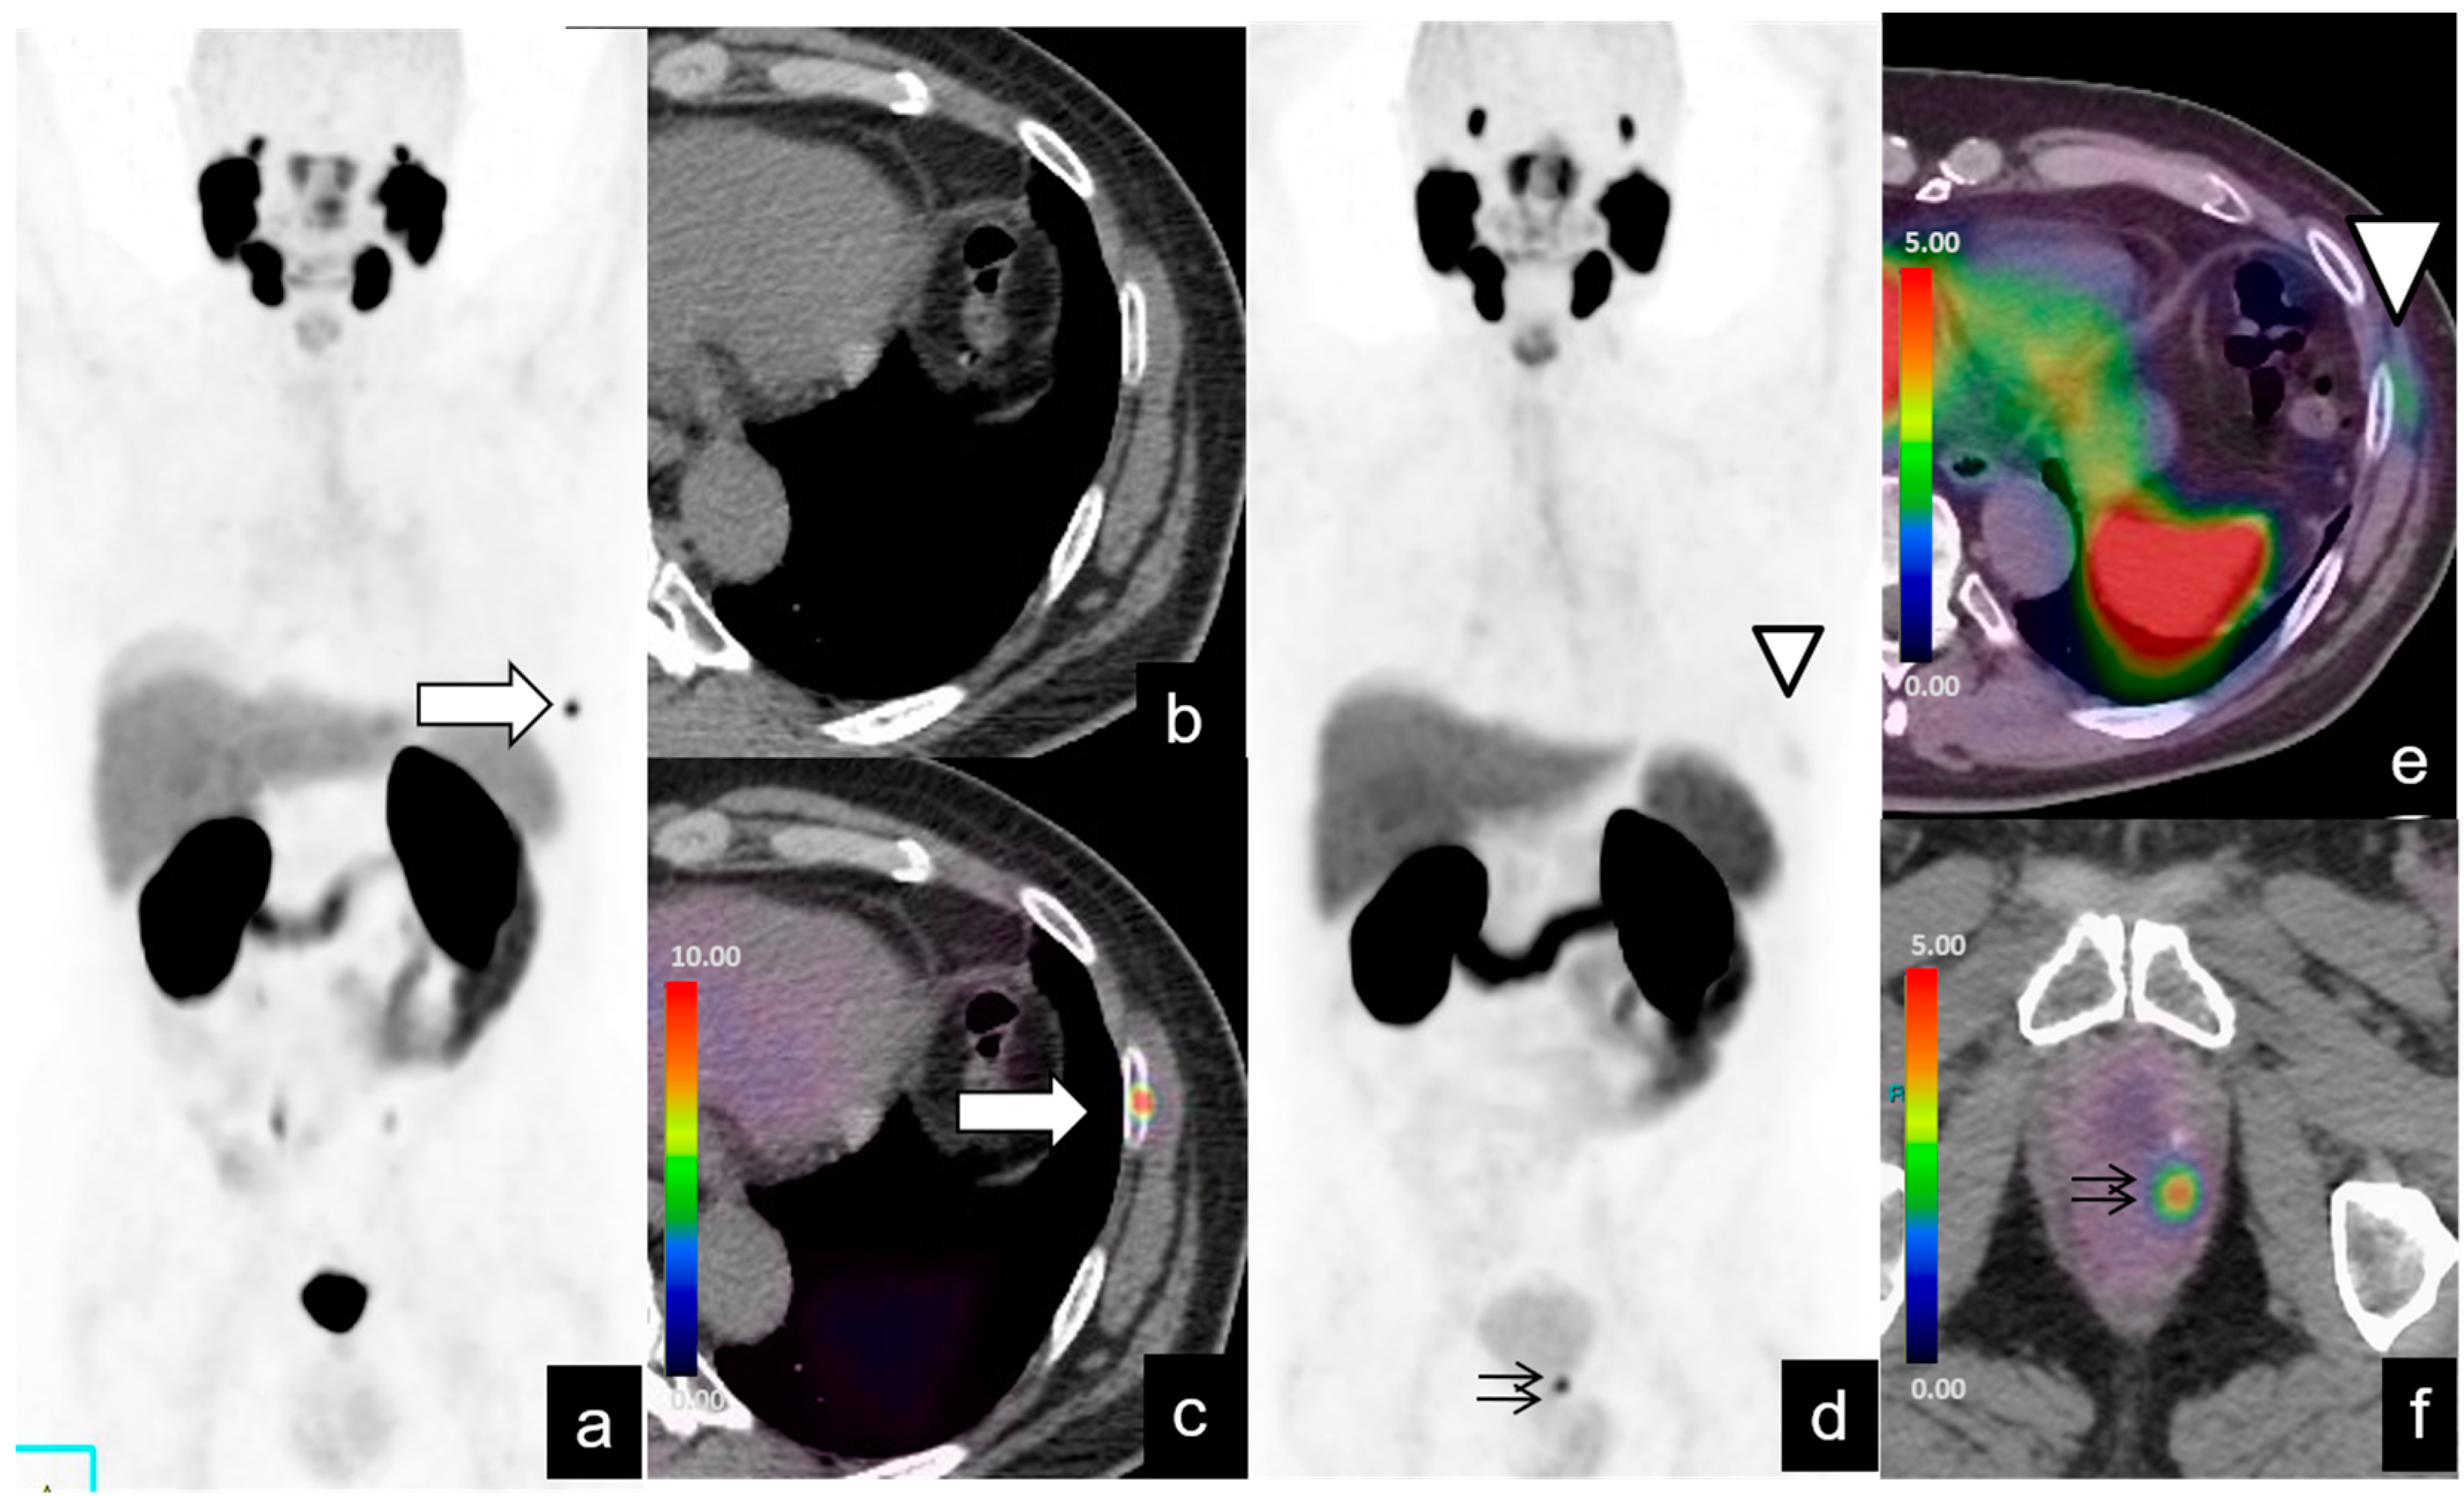

| Supradiaphragmatic | 4/128 (3%) | 27.2 | 3–60 | 18.5 | 15–22 |

| Bone metastases | 20/128 (15%) | 19 | 1.9–70 | ||

| Other (e.g., lung, liver) metastases | 5/128 (3%) | 14.6 | 2.5–17 |